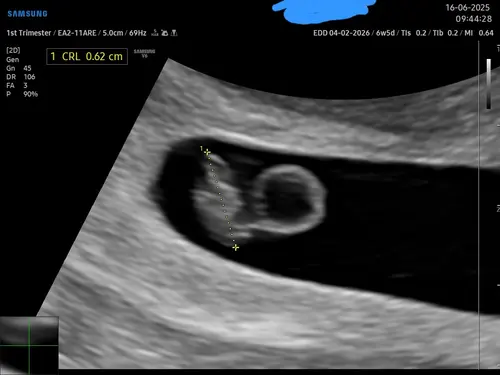

Een kloppend hartje! Super blij. 馃槃 Het is 6.2 mm en 3 dagen vroeger dan dat we dachten. De verwachte datum is nu 7 februari. Ze gaf wel aan dat het moeilijk te zien is, het is nog zo klein.